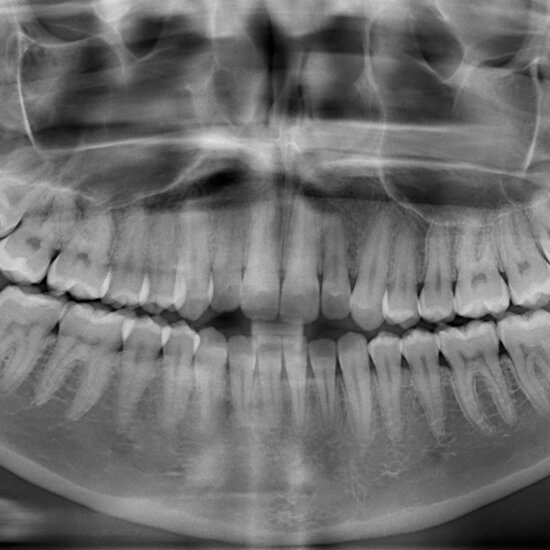

Digital X-rays have revolutionized insight into a patient’s oral health. Digital X-rays can detect a wide range of conditions but are commonly used to identify bone fractures, dental issues, and misalignment. At your appointment, what our dentist can detect will vary on the type of dental X-ray taken. For example, panoramic X-rays provide an entire view of the mouth in a single image, while a bitewing dental X-ray shows the upper and lower teeth in one area of the mouth.